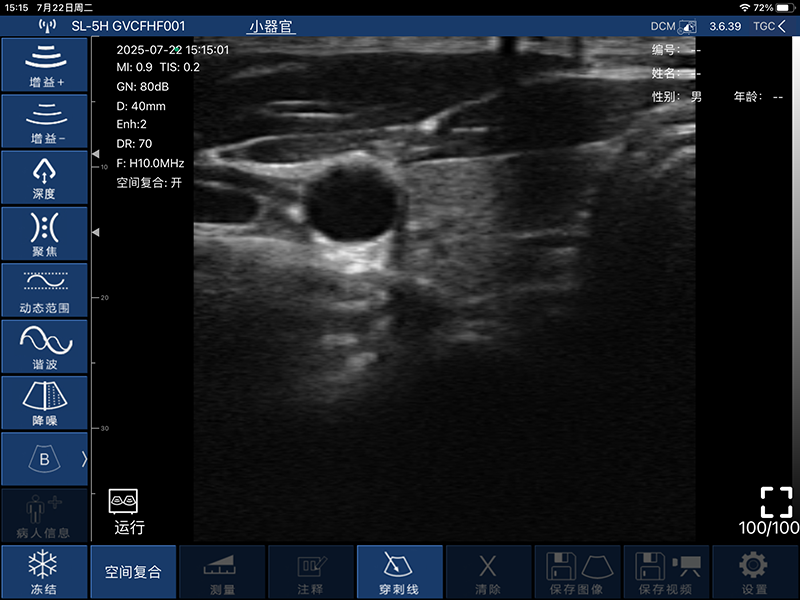

带指套探头的掌上彩超,小小的掌超主机放在口袋可随处走,手指套着探头即可完成打图成像,让手不再需要握着探头而可解放出来还能拿其他东西,特别适合术中等应用

- 穿刺辅助功能:平面内穿刺引导线功能,平面外穿刺引导与血管自动测量功能

- 显示模式:B、B/M、COLOR、PDI、PW

- 图像调节:增益、焦点、反相脉冲谐波、降噪